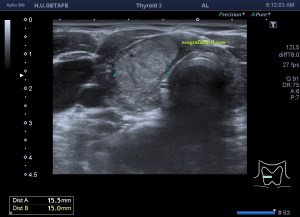

Era un nódulo hiperecogénico en el contexto de la tiroiditis en el estudio de una ecografía tiroidea.

Te enseño las imágenes, típicas de una exploración tiroidea de protocolo con semiología de tiroiditis.

De la imagen 1 a 7 el protocolo habitual, el estudio particular del nódulo con medidas y aplicación del doppler demuestra el aspecto típico del Caballero Blanco.

De la 8 a la 11 estudio con Doppler.

La imagen 12 y 13 están adquiridas con una sonda de 18 Mhz.

En la 14 un ganglio reactivo con medidas respetadas.

El el 15 tienes un vídeo de un corte axial de El Caballero Blanco.

Resumen de las imágenes que has visto en el caso de hoy:

1. Hipoecogenicidad del parénquima

2. Heteroecogenicidad

3. Múltiples nódulos hipoecoicos muy pequeños

4. Doppler Color y Doppler Power aumentado de tamaño en el nódulo

Este es el aspecto ecográfico descrito anteriormente de la patología que habitualmente puede albergar el nódulo del que trata hoy el post y que no es otra que la de la Tiroiditis de Hashimoto.

El Caballero blanco, recibe el nombre debido a su semiología hiperecogénica, homogénea y solitaria circunscrito en la patología referida con anterioridad, puede aparecer en esta patología de forma benigna o degenerar en otro tipo de patología a formas malignas como el linfoma tiroideo.